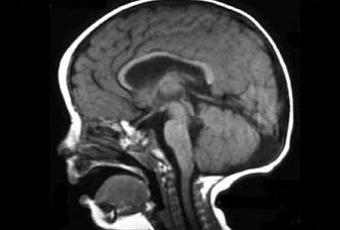

La enfermedad presenta una complejidad muy grande como para resumir sus causas. Sin embargo, básicamente puede describirse como una malformación en el mesencéfalo y en el vermis del cerebro, encargado de la movilidad de las células que comprenden el líquido cefálico.